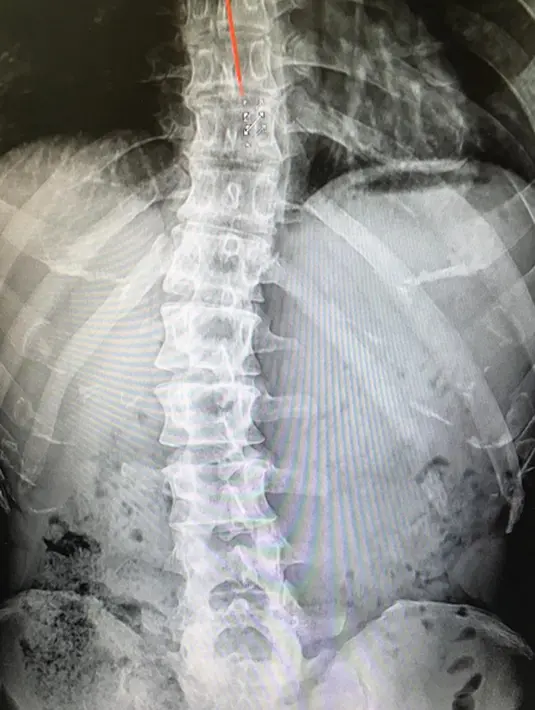

Melansir Allkpop (4/11), Jong Kook mengunggah foto hasil rontgen pada bagian belakangnya. Ia menuturkan alasan dirinya menjalani tugas tersebut. (Instagram/kjk76)

Dalam foto itu, Jong Kook menyatakan bahwa ia menderita skoliosis, yaitu melengkungnya bagian tulang belakang secara tidak normal. Pasalnya gangguan ini kerap terjadi pada masa anak-anak sebelum pubertas. (Instagram/kjk76)

Artis Korea ini juga menjelaskan alasannya membentuk tubuh kekar dan berotot. Semua itu lantaran ia ingin lakukan sesuatu yangdapat menyanggah tulang belakangnya. (Instagram/kjk76)

“Aku masih membentuknya, lantaran aku harus melakukan sesuatu untuk menyanggah tulang belakangku yang melengkung,” tulis Kim Jong Kook dalam unggahan fotonya tersebut. (Instagram/kjk76)

Resah dengan komentar masyarakat yang mengatakan dirinya bohong. Ia mengungkapkannya dengan mengatakan bahwa ia tak nyaman alami gangguan ini, bahkan ia juga alami gangguan tidur. (Instagram/kjk76)

Dengan mengunggah foto hasil rontgennya di Instagram, Kim Jong Kook menuliskan segala keresahan yang selalu menyudutkan dirinya yang dianggap berbohong. (AFP/Bintang.com)